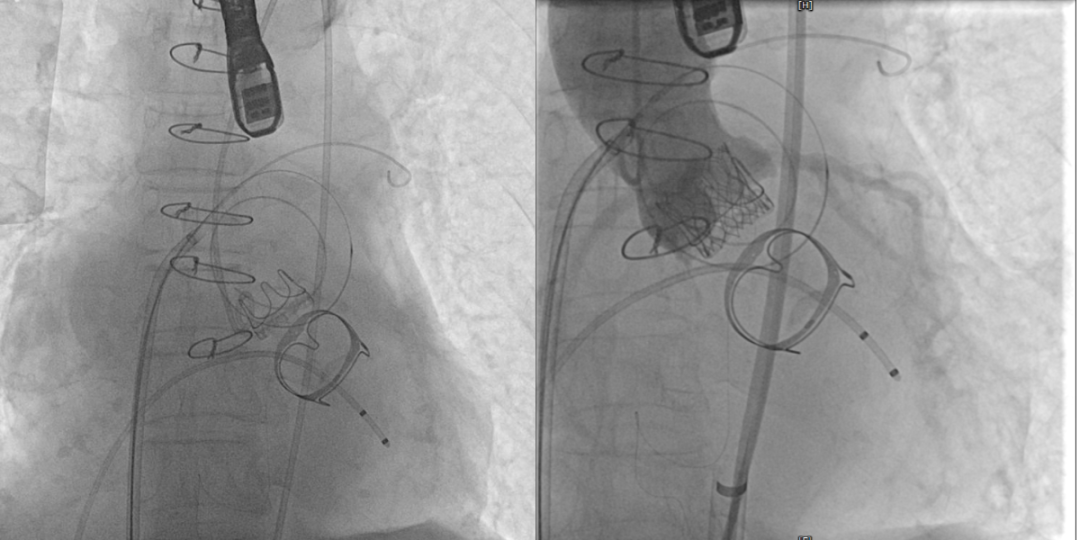

术前(图1)和TAVR 植入(图2)

在经过术前CTA评估测量等检查后,正式手术在珠海市人民医院医疗集团的百级层流复合手术室内进行,在林阿姨全麻的情况下使用食道超声及X线监测指引,经过3小时的紧张手术,双瓣中瓣手术最终成功完成。

经过充分的术前食道超声及心脏CTA的评估,团队一致选择目前国际上瓣中瓣(Valve in Valve)技术使用最多最成熟的器械——Edwards SAPIEN3瓣膜。与林阿姨及其家属充分沟通后,在经验丰富的王焱院长的指导下,珠海市人民医院结构性心脏病团队决定为林阿姨同期进行主动脉瓣及二尖瓣的双瓣膜置换,采用的方案是先经股动脉途径为其行主动脉瓣的瓣中瓣植入(VinV TAVR),然后经股静脉途径,穿刺房间隔后,行二尖瓣的瓣中瓣植入(VinV TMVR),视情况对房间隔穿刺后的缺损进行封堵。